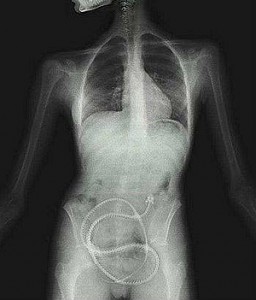

Una mujer de Iowa, Estados Unidos, compró una lombriz solitaria por internet y se la tragó con el único propósito de perder peso.

La mujer, a los pocos días de introducir el parásito en su estómago comenzó a sentir dolores, razón por la que consultó al médico. La sorpresa fue mayúscula tras la confesión y el doctor que la atendió quedó tan impactado que llamó al departamento de Salud Pública para que lo guiaran.

Si bien las lombrices solitarias pueden aparecer en el cuerpo humano al consumir carne cruda, no es conveniente introducirlos de forma voluntaria al estómago porque puede absorber suficiente comida como para provocar desnutrición.